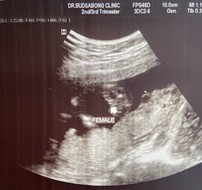

แม่ๆช่วยดูหน่อยชายหรือหญิง ค่ะ 😛🥰

วันนี้ไปหาหมอมาคุณหมอก็ยังไม่ยืนยันว่าชายหรือหญิงค่ะ บอกแค่ว่าน่าจะหญิงนะ มีกลีบๆไม่มีอะไรโผล่แต่ก็ยังเล็กไม่มั่นใจ อิแม่อยากเตรียมของแล้วค่ะ( ปัจจุบัน 19 วีค 6 วันค่ะ)

นอนท่าคล้ายๆกันเลยค่ะหมอบอกดูยากแต่ก็หมุนไปหมุนมาจนเห็นบ้านนี้ได้ลูกสาวค่ะ🥰

เหมือนบ้านนี้เลยค่ะ หมอบอกผญ80% แต่ต้องมาดูเดือนหน้าอีกที แต่แม่ก็แอบดีใจ 🥰🥰🥰

ของแม่น่าจะผญ.นะคะ แต่บ้านนี้ชัดเลยค่ะ